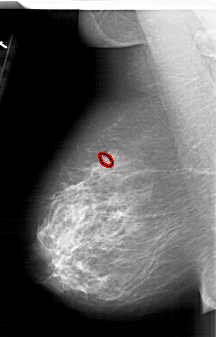

A_1626_1.LEFT_MLO

FILE: A_1626_1.LEFT_MLO.OVERLAY

TOTAL_ABNORMALITIES 1

ABNORMALITY 1

LESION_TYPE CALCIFICATION TYPE PLEOMORPHIC DISTRIBUTION CLUSTERED

ASSESSMENT 4

SUBTLETY 2

PATHOLOGY MALIGNANT

TOTAL_OUTLINES 1

BOUNDARY